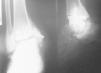

Fig. 7.--Radiografía simple, anteroposterior y lateral, de tobillo derecho tras la implantación de la prótesis. Se aprecia reabsorción ósea periprotésica con movilización del implante. Caso clínico núm. 2.

Fig. 7.--Plain radiographs, anteroposterior and lateral, of the right ankle after prosthesis implantation. Periprosthetic bone resorption with implant mobilization is evident. Clinical case 2.

Se presenta el caso de un paciente de veintisiete años, sin antecedentes personales ni familiares de interés, que sufre una fractura-luxación de tobillo derecho que es reducida y fijada con una placa en maleolo peroneo y dos tornillos en maléolo tibial.

A los tres años de la intervención, presenta molestias generalizadas en tobillo derecho que son cada vez más intensas por lo que se decide la extracción del material de osteosíntesis. A pesar de ello, el dolor persiste y en la radiografía simple se observan signos artrósicos evidentes en la articulación tibioastragalina y se le propone la colocación de una prótesis de tobillo.

A los 20 días de la implantación de la prótesis, comienza con un cuadro de fiebre, dolor y supuración en tobillo. Se realiza una gammagrafía ósea en la que se observa una hiperactividad en tobillo derecho sospechosa de complicación séptica. La gammagrafía con galio muestra un depósito patológico del mismo que afecta a estructuras posteriores de la articulación y que resulta compatible con infección.

En la actualidad, presenta movilización e infección de la prótesis y se propone la realización de una artrodesis de tobillo.